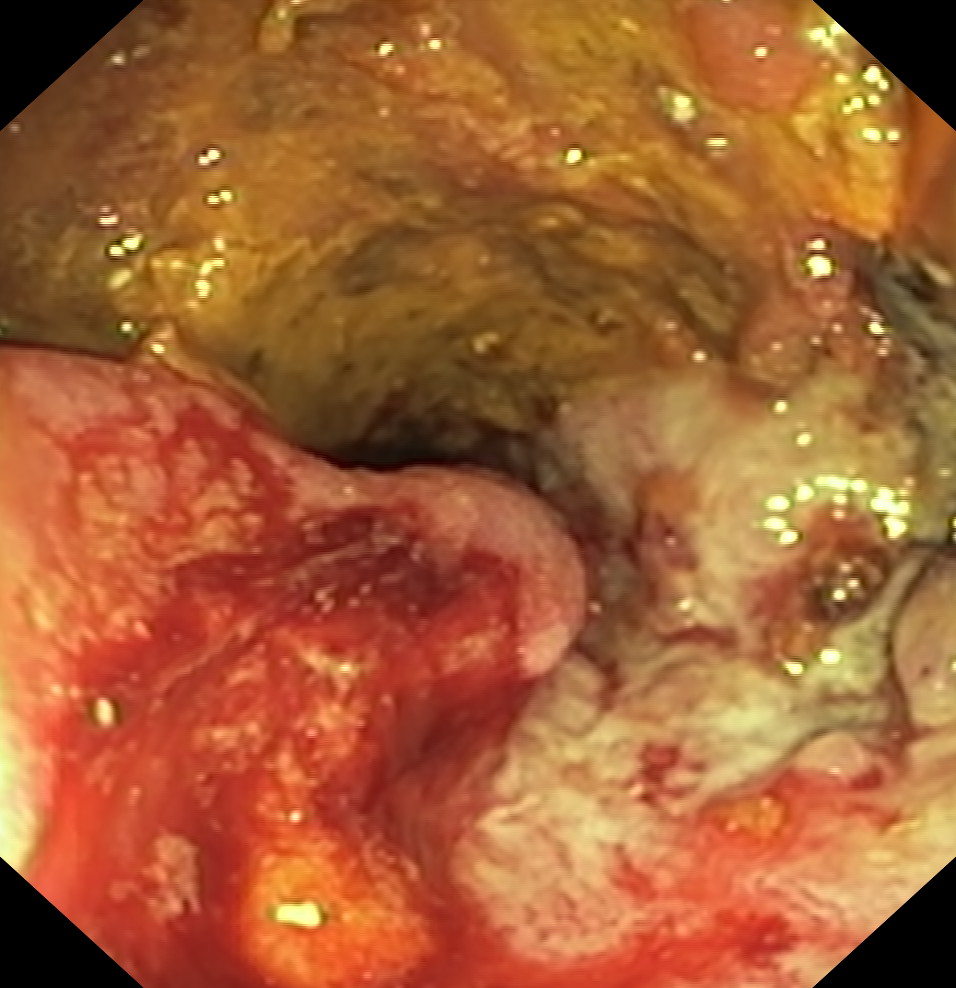

Nowotwory przewodu pokarmowego